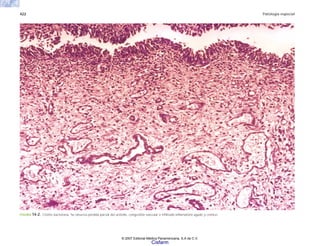

Ganglios linfáticos